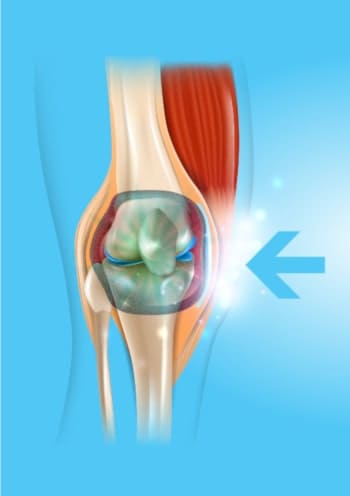

La articulación y la columna se desgastan con el paso de los años, pero si también se rompen por el sobrepeso, el trabajo físico extenuante, el transporte de objetos pesados, el exceso de deporte, las lesiones y los hematomas. El líquido sinovial y el cartílago han sido destruidos. Las juntas suenan como un tamiz sin lubricar: empieza a desgastarse y a degradarse constantemente. Con el tiempo, comienza a sentirse rígido y con un dolor insoportable que le impide moverse con normalidad. Si desarrollan inflamación y degeneración grave.

Desafortunadamente, las células del cartílago y del líquido sinovial no tienen la capacidad de curarse por sí mismas. Esto significa que, a diferencia de otras células del cuerpo humano, no podemos volver a estar sanos. Por eso las articulaciones y la columna empeoran día a día. Eso sí, no cambies la caminata y aprovecha las actividades diarias para proteger tus articulaciones y columna. Sería absurdo.

La fórmula única de Arthrozax actúa desde el interior del cuerpo, desactivando el dolor a nivel celular y permitiéndote seguir con tu vida sin molestias. Gracias a sus propiedades estimula la nutrición celular, lo que restablece los procesos regenerativos en un 300%. Al mismo tiempo, los ingredientes naturales inician los procesos de regeneración automática del cartílago y del líquido sinovial. El uso diario de las crema Arthrozax es suficiente para que el proceso de regeneración ocurra de forma continua las 24 horas del día. Haz lo que haces siempre y tus articulaciones y columna se rejuvenecerán y recuperarán la movilidad. De esta forma, la degeneración y el dolor desaparecen para siempre en 30 días. ¡Sin efectos secundarios!

ANTES

Articulación destruida y afectada por degeneración y dolor

DESPUÉS

Articulación regenerada: 100% sana y sin dolor